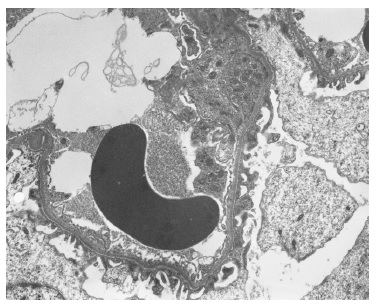

The light microscopy sample was representative only of the medullary region. The immunofluorescence (IF) sample had four glomeruli and was negative (IgG, IgA, C3, kappa and lambda). Electron microscopy (EM) revealed one apparently normal glomerulus except for markedly reduced glomerular basement membrane (GBM) thickness, varying between 83nm e 167nm (reference values: 250-350nm) (Figures 2 and 3). Beyond GBM thinning there were no other changes (such as lamellation, irregular contours or heterogeneity of the GBM). The absence of light microscopy implies the loss of valuable information such as the exclusion of mesangial proliferation or segmental/global glomerulosclerosis (importante for IgA nephropathy). Nonetheless, negative IF suggests that this diagnosis is less probable. Also, EM did not show any mesangial deposits (with the limitation of a small sample since only 1 glomerulus was present). Considering biopsy findings and benign clinical evolution (patient with stable normal kidney function and no proteinuria for more than two years of follow-up) a diagnosis of thin membrane disease was made. It should be stressed that although X-linked Alport syndrome occurs with GBM lamellation, in early stages of the disease only thinning of the basement membrane may be present (although it usually occurs with intermitente GBM lamellation).

Figure 3 Electron microscopy x5000